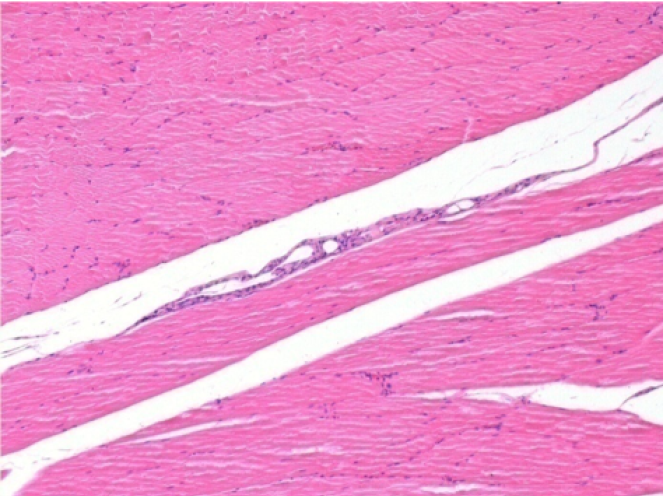

7 months (D210)after Endopeel IM Injection 0.1ml in the right pretibial muscle.

Complete Restitutio ad integrum after 7 months